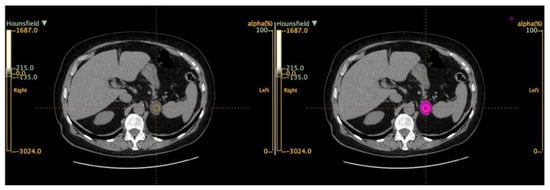

1. Introduction

2. Materials and Methods

2.3. Radiomic-Based Machine Learning Modeling